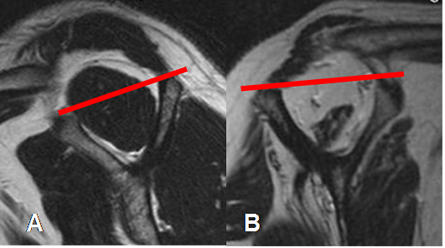

La atrofia del músculo supraespinoso es un signo de cronicidad y se correlaciona con el resultado quirúrgico. (2). Se valora con el signo de la tangente, en un corte sagital. El supraespinoso debe cruzar la línea trazada entre el borde superior de la coracoides y la espina de la escápula. En casos de atrofia, el borde superior del músculo, se localiza inferior a esta línea. (2). (Fig 20).

Fig 20. Signo de la tangente.

A: RM sagital en T2. Supraespinoso normal, cruzando la línea tangente.

B: RM sagital en T2. Supraespinoso atrófico, por debajo de la línea tangente.